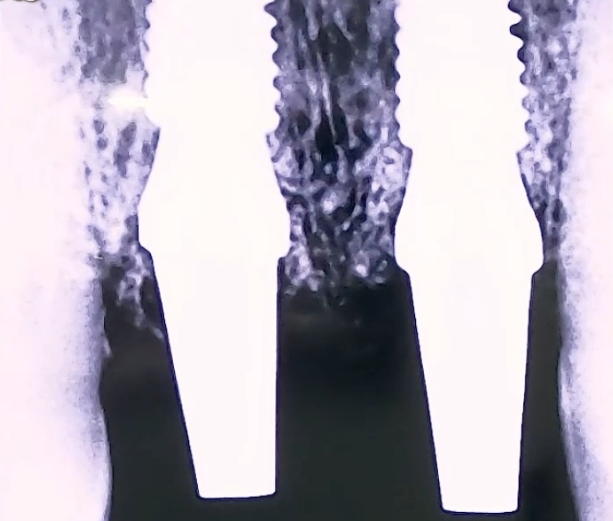

엑스레이 촬영을 해 보니 위 앞니 2개 치아의 잇몸 안쪽 뿌리 부분이 완전히 깨져 있었습니다.

만약 바깥쪽 치아 머리가 손상되었다면 보철치료로 복원해 드릴 수 있었을텐데

치아 뿌리가 부러졌기 때문에 자연 치아를 살리는 것이 불가능해 임플란트를 진행하였습니다.

부러진 앞니 2개를 발치한 후 당일 임플란트 식립과 임시치아 제작까지 해 드렸습니다.

임플란트가 단단히 자리잡을 수 있도록 뼈이식과 함께 식립하였고,